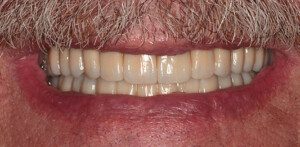

Smile GalleryImplant RestorationsFull Mouth Implant Restoration 1 of 13 Pre-operative smile Pre-operative smile Pre-operative frontal view, lips retracted Pre-operative panoramic image (note bone levels) Post-surgical panoramic image Surgical temporary bridge (note convex contours) Delivery of surgical temporary bridges in both upper and lower Two weeks post-op surgery and temporaries (note amazing tissue response) Three months post- surgery. (Note tissue development) Definitive implant bridges (FP-2) Post-treatment panoramic image Final result smile Final result smile